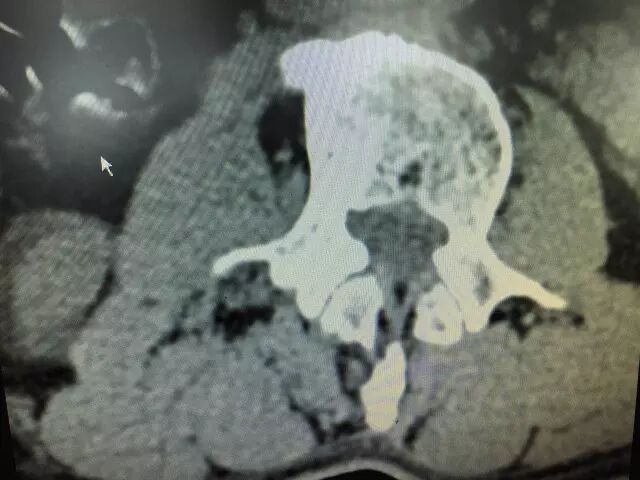

CT检查方便、组织密度分辨率高,广泛用于椎间盘突出症的诊断。

不足之处是有辐射,只能做横断面扫描,对软组织的分辨力不足,无法显示椎间盘的解剖和神经。(约320元)